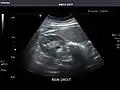

Renal ultrasonography

Ultrasonography of the kidneys is essential in the diagnosis and management of kidney-related diseases. The kidneys are easily examined, and most pathological changes in the kidneys are distinguishable with ultrasound.[7]

Kidneys: Right and left kidneys measure 11.5 cm and 12 cm in length respectively. No hydronephrosis. Small left lower pole kidney cyst.

Right kidney -